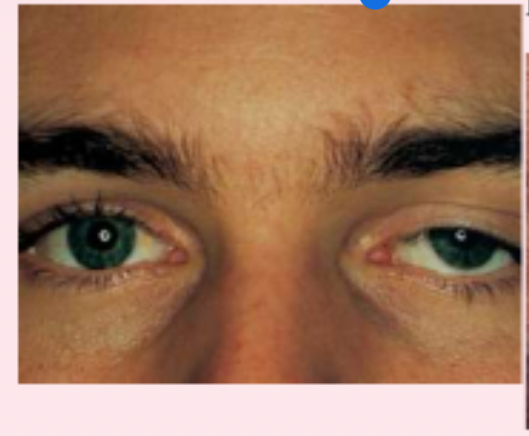

exophthalmos

protruding eyeballs and retracted eyelids